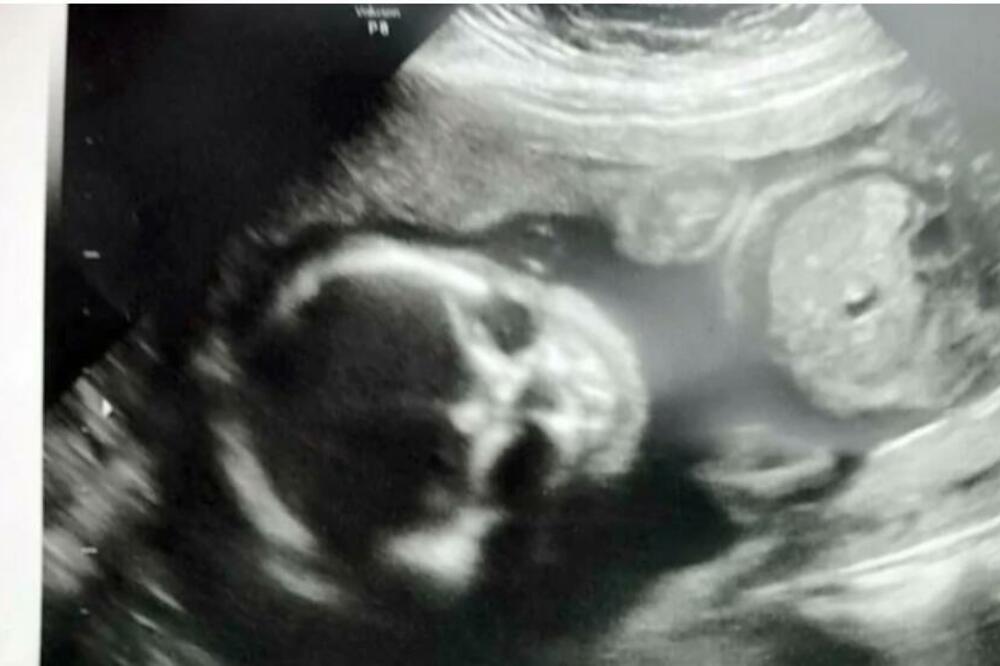

OTIŠLA JE NA ULTRAZVUK U 21. NEDELJI TRUDNOĆE: Čim je videla kako BEBA IZGLEDA NA SLICI, nije ŽELELA DA SE PORODI

Džesika, koja je u tom momentu imala samo 22 godine, priznaje da joj je beba na ultrazvuku delovala toliko jezivo i zastrašujuće da je poželela da do porođaja ni ne dođe.

U 21. nedelji trudnoće otišla sam na ultrazvuk - kada sam videla ovu sliku svog nerođenog sina, uplašila sam se porođaja, kaže Džesika Vuds, sada 27-godišnjakinja, koja je pre nekoliko godina rodila zdravog i pravog sinčića. Ipak, ultrazvuk u 5. mesecu trudnoće uterao joj je strah u kosti.

Ako ga bolje pogledate zaista je neobičan, ali bila je reč samo o optičkoj iluziji - Silas je zaista simpatičan mališan.